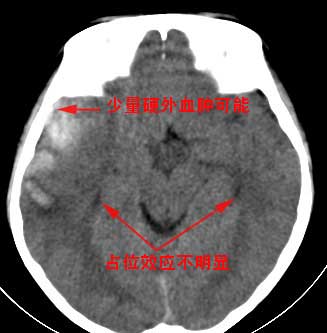

外伤一天,m,21y,骨窗示右颞骨骨折.

请大家看看,是脑内还是脑外(硬膜下还是硬膜外).请说说理由.谢谢.

右侧颞部硬膜外血肿,并右侧颞叶脑挫裂伤,

脑内脑外全有,上方比较局限近似梭形改变,考虑硬膜外血肿。没有跨过颅缝,且是脑膜中动脉所在的位置。中线移位,占位效应明显。后方条带状增高影,周围有水肿带,考虑脑内血肿。

右颞区硬膜外血肿伴右颞叶脑挫裂伤,依据

1出血灶局限,硬膜下出血广泛

2边缘光滑,硬膜下出血边缘不清楚

3出血合并骨折,硬膜下出血合并骨折的少

4在外伤的同侧,硬膜下出血可以在同侧,也可以在对侧

不典型硬膜外血肿合并脑挫裂伤.

右颞叶见混杂密度灶(以高密度灶为主)右侧脑室受压变形,中线结构左移,右颞部颅骨内板下见弧形高密度灶,右侧裂池及部分脑沟内见高密度灶;

结论:1:右颞叶脑挫裂伤;

2:右侧硬膜下血肿;

3:蛛网膜下腔出血。